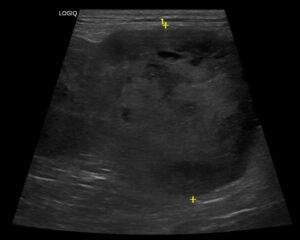

Vereproovides ilmnes vaid kerge põletikunäitajate tõus, kuid ultraheliuuringul tuli välja murettekitav leid – Chilli põrnas oli avastatud muutus, mille struktuur viitas võimalikule kasvajale.

Chilli saadeti nädalavahetuseks koju toetavale ravile ja jälgimisele. Esmaspäeval tehtud kordusultraheli näitas aga, et põrnas olev moodustis oli vaid mõne päevaga selgelt muutunud. Selline muutus viitas sellele, et tegemist võib olla rabeda struktuuriga kasvajaga, millega kaasneb suur risk – põrna ootamatu rebenemine, mis on eluohtlik seisund.